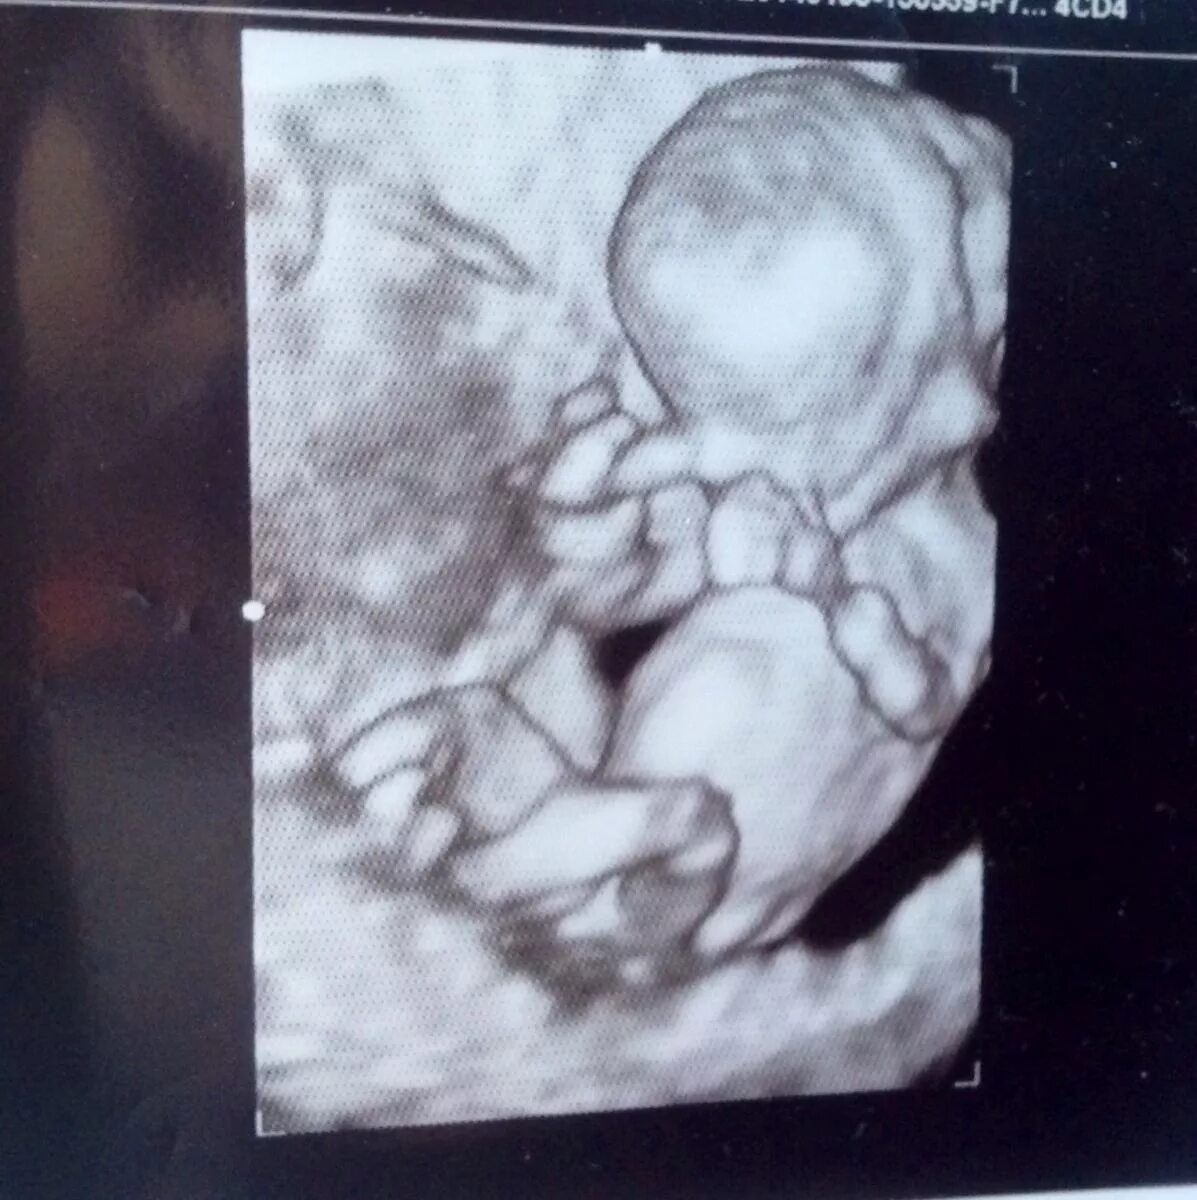

13 недель как выглядит малыш